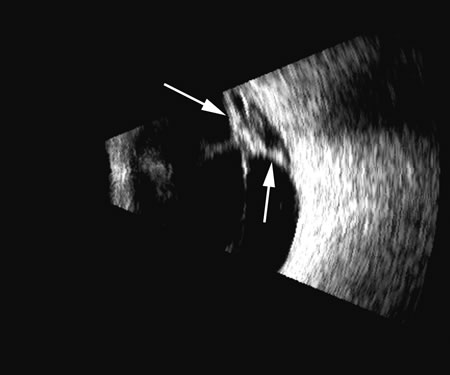

| CHOROIDAL DETACHMENT |

| The choroid, like the retina, is highly reflective and may resemble the retina when detached. Its thickness, which includes the retina, Bruch's membrane, and the choriocapillaris (tunica ruyschiana) is not usually differentiable when measured with routine ultrasound;12 however, it may be measured with digital techniques.18 Anatomically, the choroidal elevation is usually a smoothly round, convex surface, limited posteriorly by the vortex veins and anteriorly at any point up to the base of the iris (Fig. 17). The choroidal space should be examined for echoes (blood) or a clear zone, as seen with effusion or the serous part of a hemorrhage. In evaluating membranes from retina or choroid, it is always helpful to repeat the examinations at a later time. |